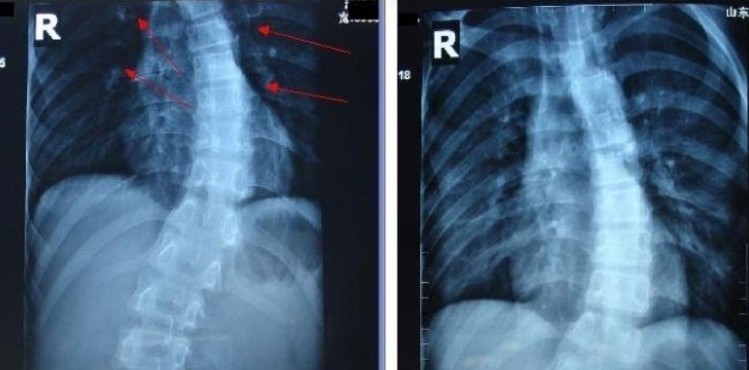

楼先生当时拍的片子